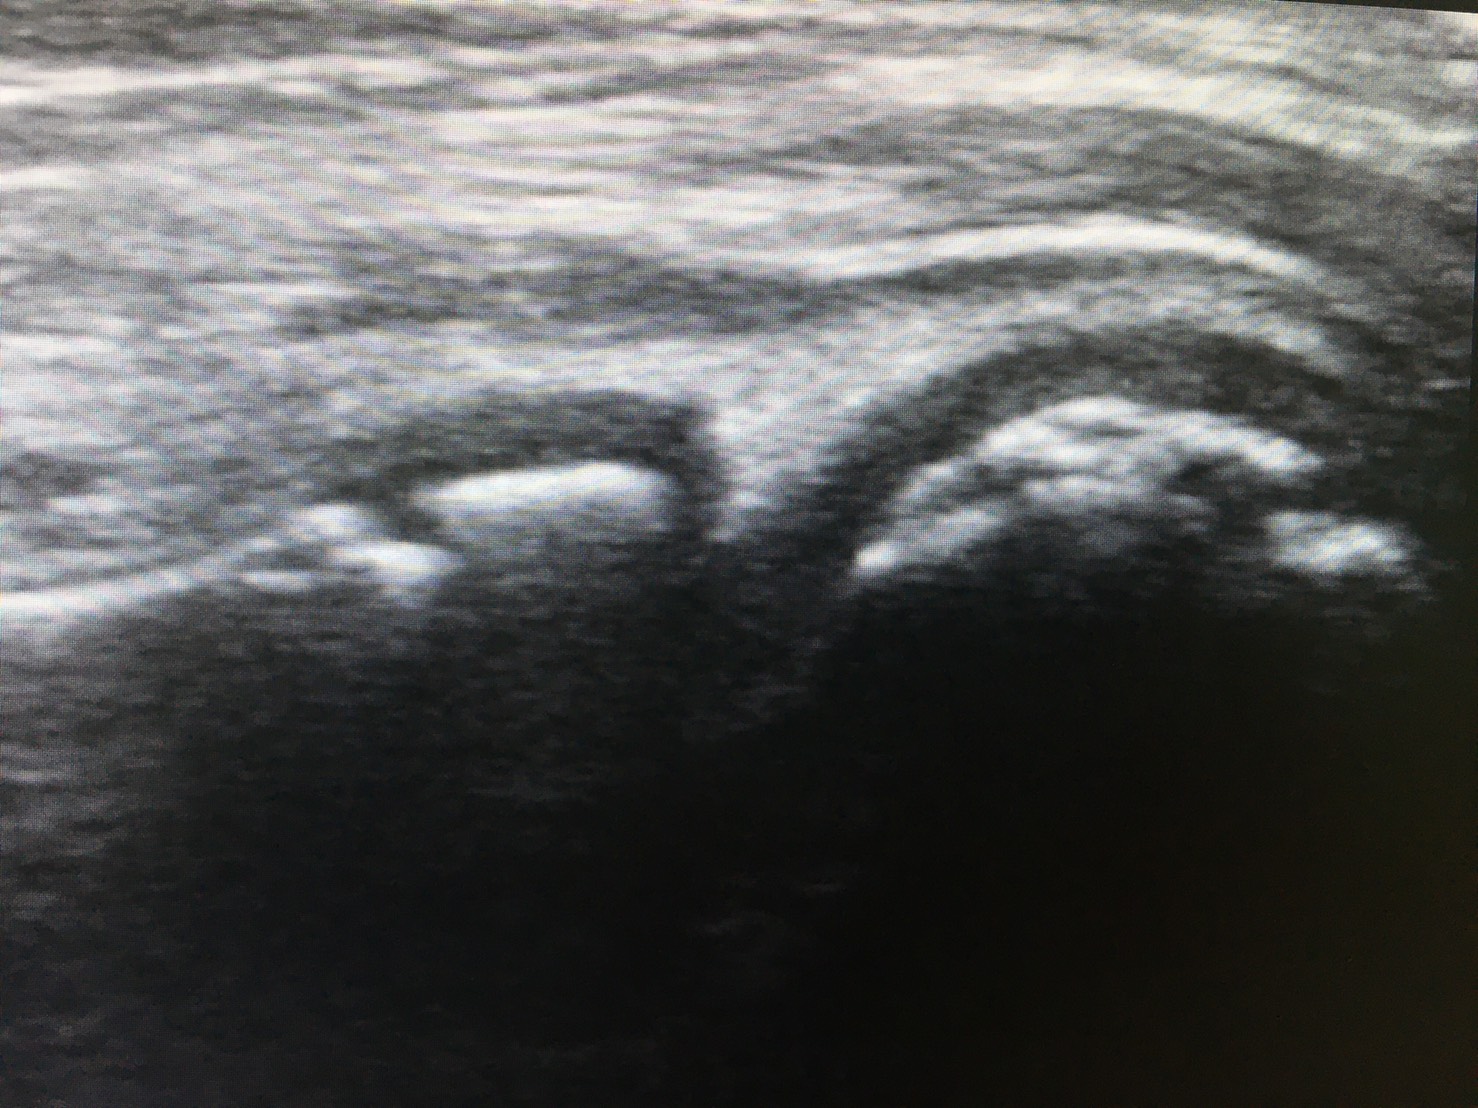

超音波検査は有用なツール

近年の超音波検査の機能は著しく向上しており、筋、関節包、滑膜、関節軟骨、軟骨下骨を明瞭に描出することができます。

超音波検査によって離断性骨軟骨炎を早期に発見できれば、保存的に治癒する可能性は高くなります。

(引用:肩と肘のスポーツ傷害より)